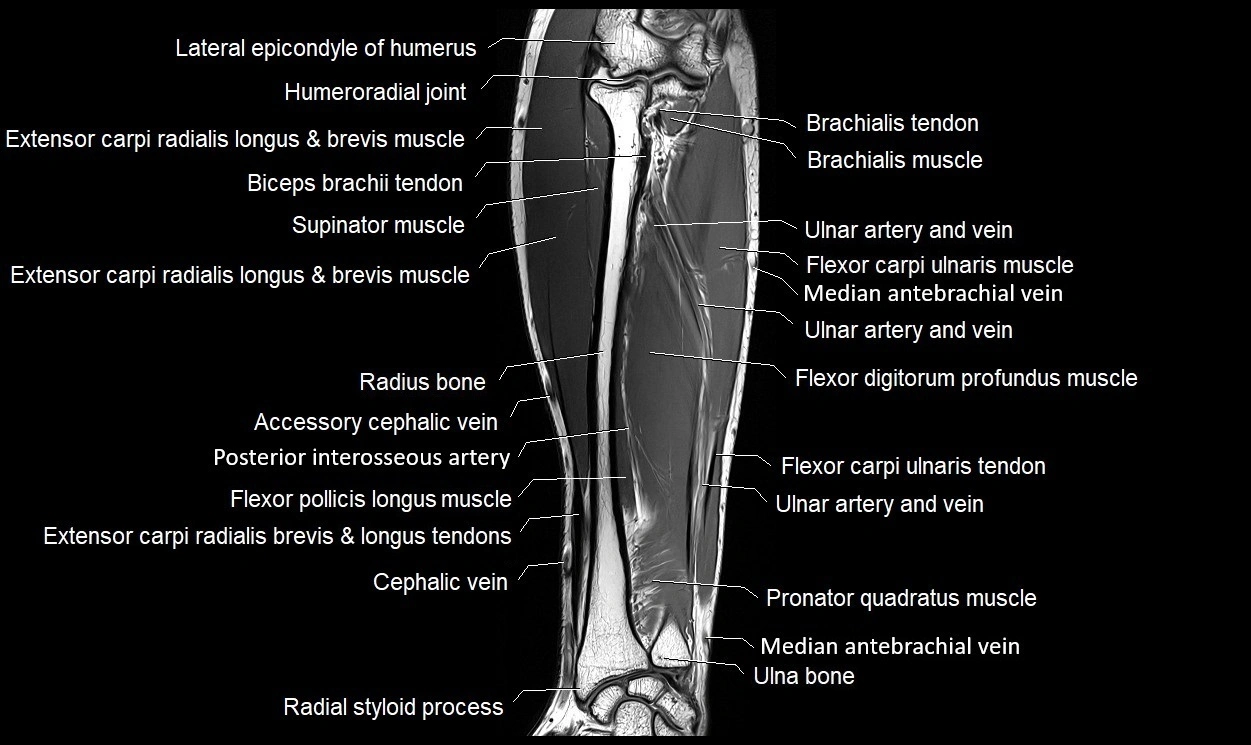

MRI images

image